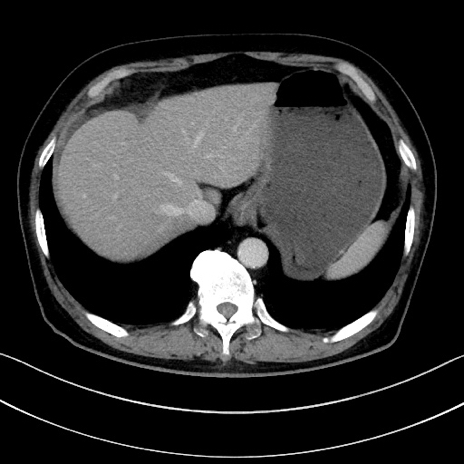

症例15(横断像)

【症例】70歳代男性

【主訴】腹痛

【現病歴】今朝から腹痛あり。全体的に痛い。特に左上の方。排ガスが今日はない。冷や汗が出る。

【既往歴】直腸癌術後

【身体所見】左側腹部〜上腹部に圧痛あり。腹膜刺激症状明らかなではない。軽度反跳痛。左下腹部に術後瘢痕あり。

【データ】WBC 7700、CRP 0.02